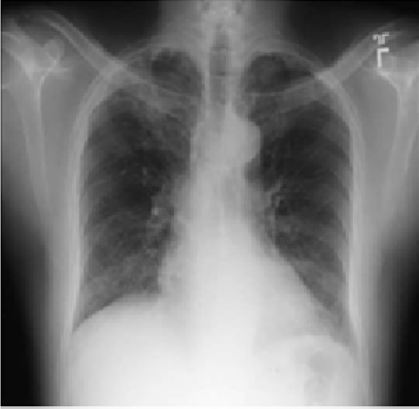

Diffuse Alveolar Hemorrhage Due to Synthetic Cannabinoid Inhalation

Mark H Adelman*, Michael Thorp,Young Im Lee, Robert L Smith